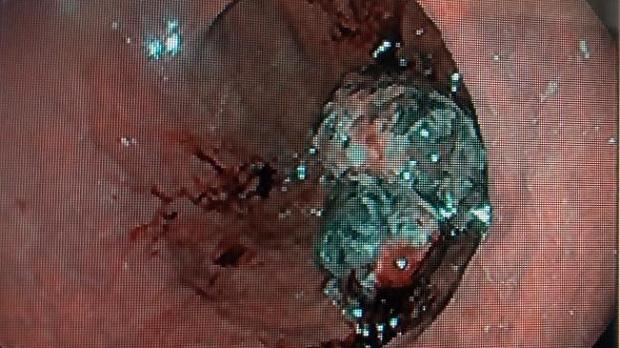

Клинические случаи: Метастаз пигментной меланомы в желудок

Пациентка 26 мет, кормящей мама, ребенку год, обратилась с интенсивными болями в  области желудка. Из анамнеза несколько лет назад удаление образования (родинки?) на плече размерами около 1 см.

в настоящее время в теле и антральном отделе несколько опухолевилных образований более 2.0 см с черным пигментом и множество плоских образований черного цвета. В гистологии  метастаз пинментной меланомы с распадом.

на коже бугорковые образования с черным пигментом.